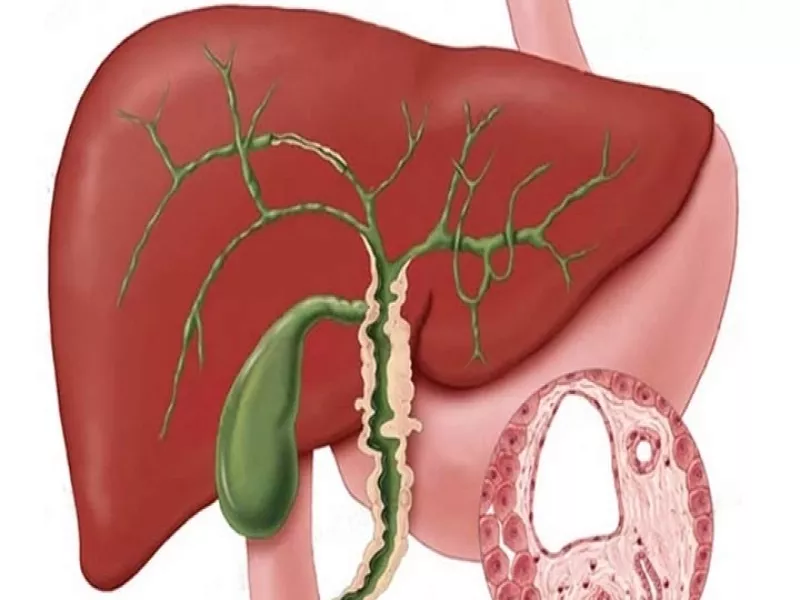

درد کبد کجای بدن است؟ این سوالی است که بسیاری از افراد هنگام احساس ناراحتی در ناحیه شکم به دنبال پاسخ آن هستند. کبد، یکی از حیاتیترین اندامهای بدن، در سمت راست فوقانی شکم و زیر دندهها قرار دارد. این عضو مسئول تصفیه سموم، تولید صفرا و متابولیسم مواد مغذی است.

محل دقیق کبد در بدن کجاست؟

موقعیت آناتومیکی کبد:

- سمت راست بالای شکم (درست زیر قفسه سینه)

- محدوده بین دندههای ۵ تا ۱۰ سمت راست

- در مجاورت اندامهایی مانند:

- کیسه صفرا (در زیر کبد)

- دیافراگم (در بالا)

- کلیه راست (در پشت)